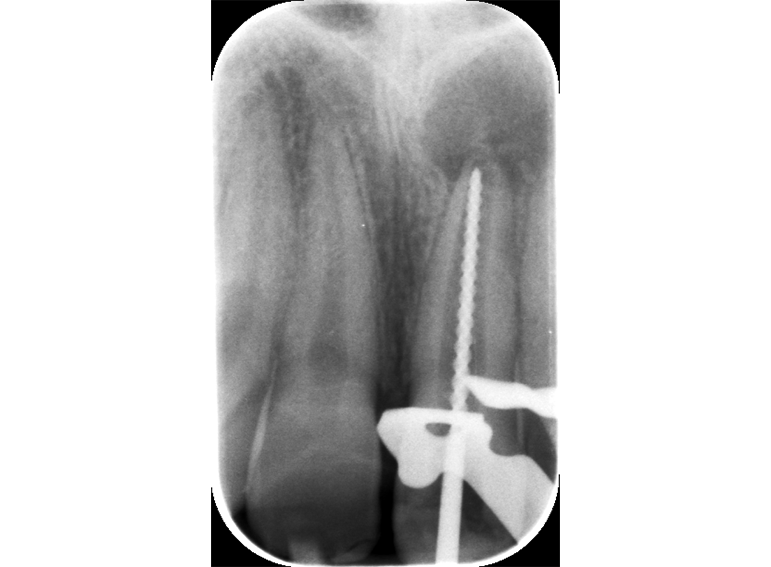

Root canal treatment including apexification of an immature incisor following dental trauma.